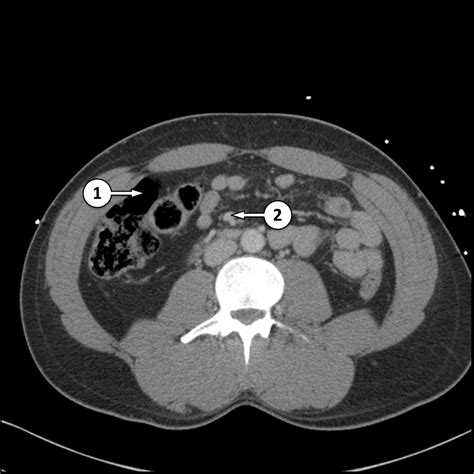

Common Findings in a Normal Abdominal CT Scan

When a Normal Abdominal CT scan is performed, several key findings are expected:

• Clear Organs: The liver, spleen, pancreas, and kidneys should appear clear and free of any masses or cysts.

• Intact Bowel: The intestines should be intact with no signs of inflammation, obstruction, or perforation.

• Normal Vascular Structures: Blood vessels should be clear and free of any blockages or aneurysms.

• No Fluid Accumulation: There should be no abnormal fluid accumulation in the abdominal cavity.